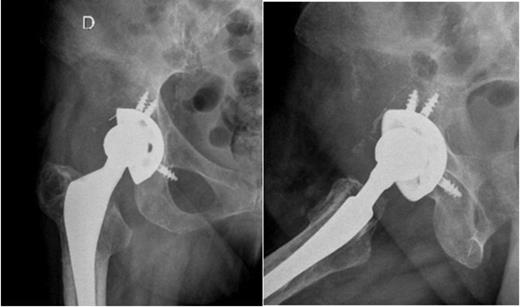

Given these findings, it was interpreted as aseptic loosening of the acetabular component and the patient was proposed for revision surgery. Two months later, when the patient was admitted for surgery, there was onset of right hip pain out of proportion associated with inability to walk, weight loss and respiratory symptoms. We asked for new pelvic and hip radiographs that showed an extensive osteolytic lesion with neoplastic appearance (Fig. 2).

Right hip radiographs (AP and lateral) at the admission, two months later, with an extensive osteolytic lesion in the right iliac wing